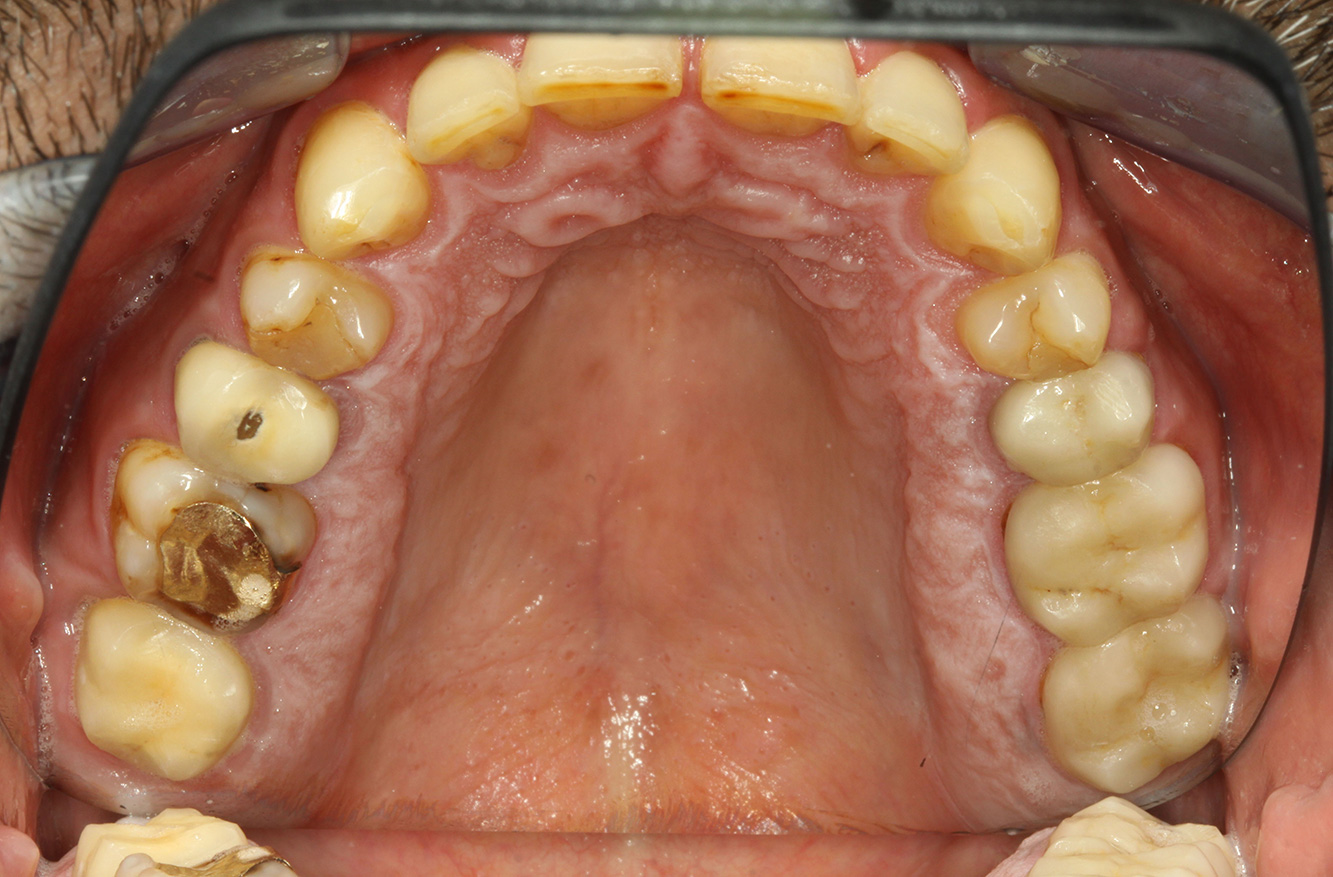

Fotos: © Dr G. Schmalz y Dr D. Ziebolz MSc

El paciente tiene 39 años con valvuloplastia frente a una insuficiencia valvular y endocarditis. Toma regularmente ASS 100 (ácido acetil salicílico) como anticoagulante. En el ámbito del estilo de vida, la alimentación se identifica como promotora de caries, ya que suele consumir alimentos azucarados y seis o siete comidas al día. La salud oral del paciente muestra un riesgo medio de caries con lesiones activas. El riesgo de periodontitis es bajo, presenta gingivitis. Se hacen las siguientes recomendaciones para el tratamiento profiláctico.